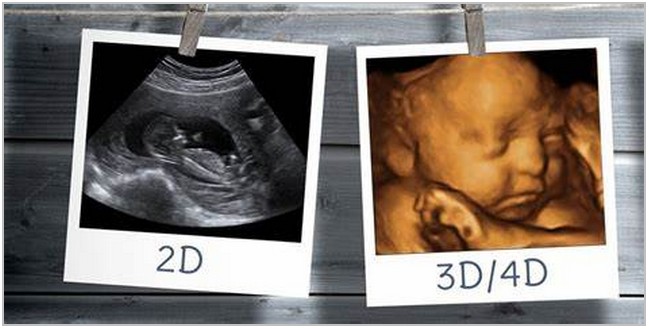

Usg 3 Dimensi

Kenali Cara Membaca Hasil Usg Untuk Tahu Kondisi Bayi Ibupedia Sebenarnya Apakah Bedanya Usg 2d 3d Dan 4d Simak Berikut Ini Moms Perbedaan Usg 2 3 Dan 4 Dimensi Kapan Harus Menjalankan Usg 3 Dimensi Church79bartlett Myblog De Sebenarnya Apakah Bedanya Usg 2d 3d Dan 4d Simak Berikut Ini Moms Informasi Biaya Usg Kehamilan November 2021 Cara Membaca Hasil Usg Yang Benar Dan Akurat Bumil Wajib Tahu Berita Apa Keunggulan Usg 4 Dimensi Di Rs Kartika Kasih Berita Apa Keunggulan Usg 4 Dimensi Di Rs Kartika Kasih Pemeriksaan Kehamilan Usg 3d Untuk Calon Ibu Primaya Hospital Usg 3d 4d Ultrasonografi Empat Dimensi Usg 4d Sebagai Alat Penunjang Diagnosis Prenatal Rumah Sakit Akademik Ugm Kapan Harus Menjalankan Usg 3 Dimensi Church79bartlett Myblog De Inspirasi Baru 44 Alat Usg 3d Apa Itu Usg 2 3 Dan 4d Dan Berapa Biayanya Yuk Cari Tahu Di Sini Moms Cermati Com Usg Cara Mudah Melihat Si Kecil Yang Menggemaskan Firmankasan Com Diary Kehamilan Usg 4d Murah Meriah Ranselriri Ini Cara Membaca Hasil Usg Berdasarkan Jenisnya Jangan Bingung Lagi Ya Orami Perbedaan Antara Ultrasound 3d Dan Ultrasound 4d Hasil Terawangan Muka Dedek Bayi Dari Bebagai Dimensi Lifestyle Fimela Com 3d Ultrasound Radiology Reference Article Radiopaedia Org Pentingnya Pemeriksaan Usg 4d Rsu Nurussyifa Usg 3d Dan Usg 4d Apa Bedanya Mana Yang Lebih Baik Berita Apa Keunggulan Usg 4 Dimensi Di Rs Kartika Kasih Why To Avoid Keepsake 3 D And 4 D Ultrasounds Your Pregnancy Matters Ut Southwestern Medical Center Ultrasonografi Empat Dimensi Usg 4d Sebagai Alat Penunjang Diagnosis Prenatal Rumah Sakit Akademik Ugm Usg 4 Dimensi Harapan Ibu Hospital Usg 3d Usg 4d Usg Endokrynologiczne Sonomedika Lodz Pl 3d Ultrasound Wikipedia Usg 4 Dimensi Definisi Keunggulan Dan Cara Kerjanya Usg 6 Bulan 3 Dimensi 12 Oktober 2016 Youtube Usg 3 4 D Youtube Tips Dan Cara Melakukan Usg 3 Dimensi Yang Benar Dan Tepat Sesuai Rekomendasi Dokter Kandungan Tribunjabar Id Ini Dia Perbedaan Usg 2d 3d 4d Dan 5d Yang Ibu Hamil Perlu Tahu Bukareview Usg 4 Dimensi Definisi Keunggulan Dan Cara Kerjanya Perlukah Melakukan Usg 3d Saat Kehamilan Mamapapa Id Perbedaan Usg 2 3 Dan 4 Dimensi Cara Membaca Hasil Usg 2d 3d 4d Dengan Tepat Ini Perbedaan Usg 2d 3d 4d Dan 5d Yang Bisa Mama Pilih Popmama Com 1 Perlukah Melakukan Usg 3d Saat Kehamilan Mamapapa Id Perbedaan Usg 3 Dimensi Dan 4 Dimensi Berbagai Perbedaan Ini Cara Membaca Hasil Usg Berdasarkan Jenisnya Jangan Bingung Lagi Ya Orami Manggala Pasca Wardhana Dr Spog K K Kfm Mengenali Berbagai Usg Pada Kehamilan 3d Ultrasound Radiology Reference Article Radiopaedia Org Jual Usg 3d Zoncare I70 Di Lapak Usg Murah Bukalapak Usg 4d Video Perbedaan Usg 4d 3d Dan 2d Yang Perlu Anda Ketahui Jual Usg 3d Zoncare I70 Di Lapak Usg Murah Bukalapak Cara Membaca Hasil Usg Yang Benar Dan Akurat Bumil Wajib Tahu Fda Peringatkan Ibu Hamil Jauhi Usg Buat Kenang Kenangan Health Liputan6 Com

3d Or 4d Ultrasound Vs 2d Ultrasound Fasilitas Usg 4 Dimensi Di Rs Al Irsyad Surabaya Harga Dan Kegunaannya Rs Al Irsyad Surabaya Hasil Terawangan Muka Dedek Bayi Dari Bebagai Dimensi Lifestyle Fimela Com Membaca Hasil Usg 2d 3d Atau 4d Mana Lebih Mudah 3 Jenis Usg Dan Perbedaannya Rumah Sakit Permata Cara Membaca Hasil Usg 2d Yang Ibu Hamil Perlu Pahami Kapan Perlu Melakukan Usg 3 Dimensi Usg 3d Usg 4d Usg Endokrynologiczne Sonomedika Lodz Pl Dwitunggal Abadi Nusa Na Tviteru Contoh Hasil Usg 3 Dimensi Usg3d Usg3dimensi Usgbayi Hasilusg Bayi Usg Usgmindray Mindray Mindrayindonesia Healthcare Medical Dc70exp Dtamedika Https T Co Fhg8tapbvv Apa Bedanya Usg 2 3 Dan 4 Dimensi Pada Pemeriksaan Kehamilan Kumparan Com Jual Alat Usg Mobile 3d Zoncare Zq 9902 Murah Jual Usg 3d Zoncare I70 Di Lapak Usg Murah Bukalapak Badanie Usg 3d I 4d To Najlepszy Sposob Na Ocene Rozwoju Plodu 1 Usg Cara Mudah Melihat Si Kecil Yang Menggemaskan Firmankasan Com Usg W Ciazy Roznice Miedzy Usg 4d I 3d Cara Membaca Hasil Usg Yang Benar Dan Akurat Bumil Wajib Tahu Manggala Pasca Wardhana Dr Spog K K Kfm Mengenali Berbagai Usg Pada Kehamilan Ibu Hamil Usg 3d Janin 3 Bulan 12 Minggu Baby 3 Months 9 Weeks Jungkir Balik Nendang Nendang Youtube Inspirasi Baru 44 Alat Usg 3d Mengenal Usg 3d Untuk Melihat Janin Lebih Jelas Seperti Foto 3d Ultrasound Wikipedia Perusahaan Jepang Ciptakan Replika Janin 3 Dimensi Tekno Tempo Co Moms Ingin Melakukan Usg 4 Dimensi Simak Manfaat Serta Perbedaannya Dengan Usg 3 Dimensi Semua Halaman Nakita Perempuan Tunanetra Hamil Bisa Melihat Janin Bayinya Tribunkaltim Co Berita Apa Keunggulan Usg 4 Dimensi Di Rs Kartika Kasih Sebenarnya Apakah Bedanya Usg 2d 3d Dan 4d Simak Berikut Ini Moms 3d Ultrasound Radiology Reference Article Radiopaedia Org Apa Itu Usg 2 3 Dan 4d Dan Berapa Biayanya Yuk Cari Tahu Di Sini Moms Cermati Com Tips Dan Cara Melakukan Usg 3 Dimensi Yang Benar Dan Tepat Sesuai Rekomendasi Dokter Kandungan Tribunjabar Id 3d Ultrasound Radiology Reference Article Radiopaedia Org Co Widac Na Usg 3d 4d Manggala Pasca Wardhana Dr Spog K K Kfm Mengenali Berbagai Usg Pada Kehamilan Usg 3d Left Boy Twins Twins Boys Cover Pentingnya Pemeriksaan Usg 4d Rsu Nurussyifa 6 Tempat Usg 4d Di Depok Mulai 300k Saja Loh Jadwaloperasional Why To Avoid Keepsake 3 D And 4 D Ultrasounds Your Pregnancy Matters Ut Southwestern Medical Center Inilah Perbedaan Antara Usg 2d Dan Usg 3d Perbedaan Antara Ultrasound 3d Dan Ultrasound 4d 2d 3d 4d Ultrasound Services Usg Centre Ultrasound Diagnostic Centre Color Doppler Centre Ultrasound Centre Sonography Centre In Giripeth Nagpur Pulse Imaging And Diagnostic Centre Id 8412082973 Cara Membaca Hasil Usg 2d 3d 4d Dengan Tepat Pentingnya Pemeriksaan Usg 4d Rsu Nurussyifa Saatnya Memeriksakan Kandungan Dengan Usg 3 Dimensi Alodokter Saatnya Memeriksakan Kandungan Dengan Usg 3 Dimensi Alodokter Usg 6 Bulan 3 Dimensi 12 Oktober 2016 Youtube Diary Kehamilan Usg 4d Murah Meriah Ranselriri Perbedaan Usg 3 Dimensi Dan 4 Dimensi Berbagai Perbedaan Badanie Usg 3d 4d Perusahaan Jepang Ciptakan Replika Janin 3 Dimensi Tekno Tempo Co Pemeriksaan Kehamilan Usg 3d Untuk Calon Ibu Primaya Hospital